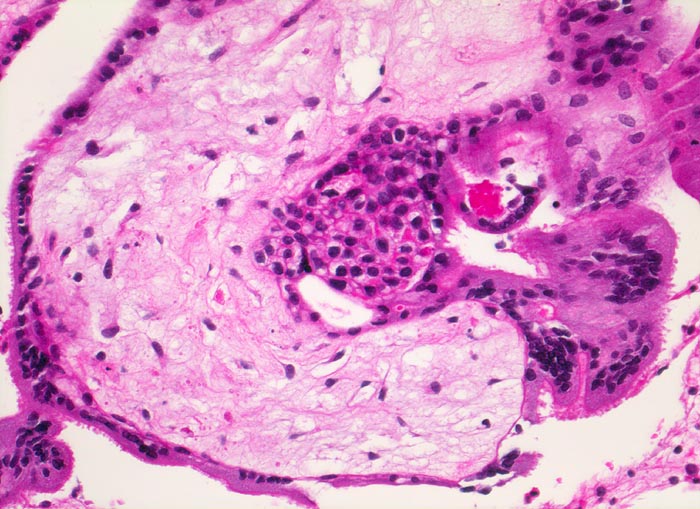

Chromosomenaberrationen verursachen nicht nur beim Feten, sondern auch an der Chorionzotte morphologisch fassbare Entwicklungsstörungen: mangelnde Verzweigungen, wandernde Trophoblastzellen im Stroma, mangelhafte Vaskularisation, hydropische Alteration des Stromas und herdförmige Atrophie oder auch Hyperplasie des Trophoblasten sind typische Befunde bei einer Chromosomenaberration. Aborte mit Triploidie zeigen in der grossen Mehrzahl das Bild einer Partialmole. Eine Tetraploidie kann das Bild einer Windmole (=Windei), einer Embryonalmole oder seltener einer Partialmole verursachen. Autosomale Trisomien können ebenfalls als Windmole oder als Embryonalmole imponieren. In nur etwa 25% aller Spontanaborte sind bei der pathomorphologischen Untersuchung ein Embryo, Embryofragmente oder ein Nabelschnuranteil nachweisbar. Die morphologische Untersuchung des Abortmaterials stellt eine wichtige Ergänzung zu den klinischen Befunden dar.

Morphologische Merkmale:

• Vergrösserte Plazentarzotten mit hydropischem Zottenstroma.

• Vereinzelt Zytotrophoblasteinschlüsse im Stroma.

• Vorwiegend einschichtiges Zytotrophoblastepithel ohne Atypien und mehrkerniger Synzytiotrophoblast. Physiologische polare Trophoblastproliferate.